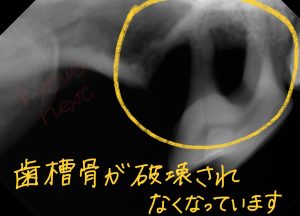

【レントゲン写真】(写真左:右上顎奥、写真左:右下顎奥)

上下ともに奥歯がひどい状態です。下顎の骨は非常にも脆くなっているのが確認できます。

何かの拍子で顎の骨が折れてもおかしくありません。